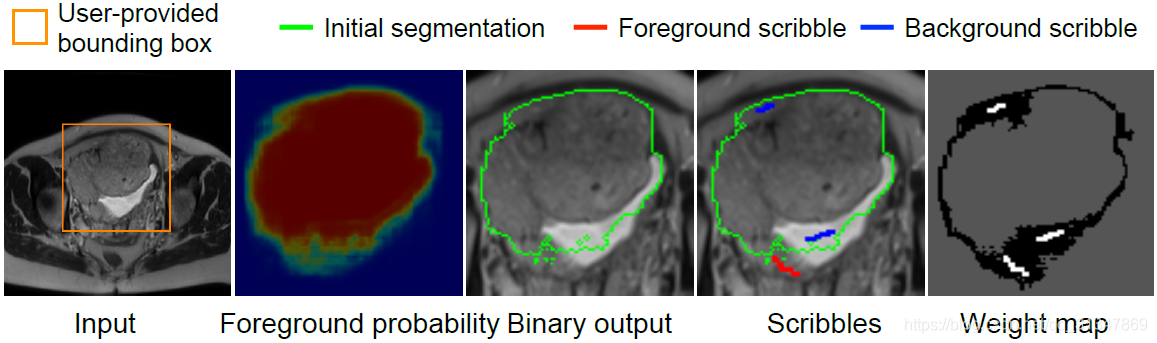

(3)Supervised Image-specific Fine-tuning:

有监督的微调需要用户在初始分割结果上画出分割不准确的地方,蓝线表示应该划分为背景,红线表示应该划分为前景。

同一个初始分割结果,同样的 scribbles,对比三种调整方法,虽然都有效果上的提升,但依然发现是 BIFSeg 的分割结果最好。